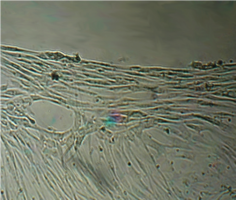

Вид монослоя и структура клеток не отличались от обычных в течение всех четырех суток наблюдения (рис. 32).

Это свидетельствует об умеренной стимуляции пролиферации фибробластов в культуре под влиянием недеминерализованной спонгиозы (таб. 9.).